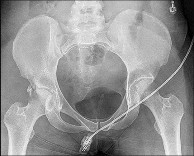

Question 1:

A 25-year-old male sustains a high-energy Pauwels type III femoral neck fracture. In a young adult with this vertical fracture pattern, which of the following internal fixation constructs biomechanically offers the greatest resistance to vertical shear forces and varus collapse?

Correct Answer: Sliding hip screw with a supplemental derotational screw

Pauwels type III femoral neck fractures have a vertical orientation (>50 degrees) and are subjected to high shear forces rather than compressive forces. Biomechanical studies have consistently demonstrated that a fixed-angle device, such as a sliding hip screw (SHS) with a supplemental derotational screw, provides superior stability against vertical shear and varus collapse compared to multiple cancellous screws in these specific high-angle fractures.